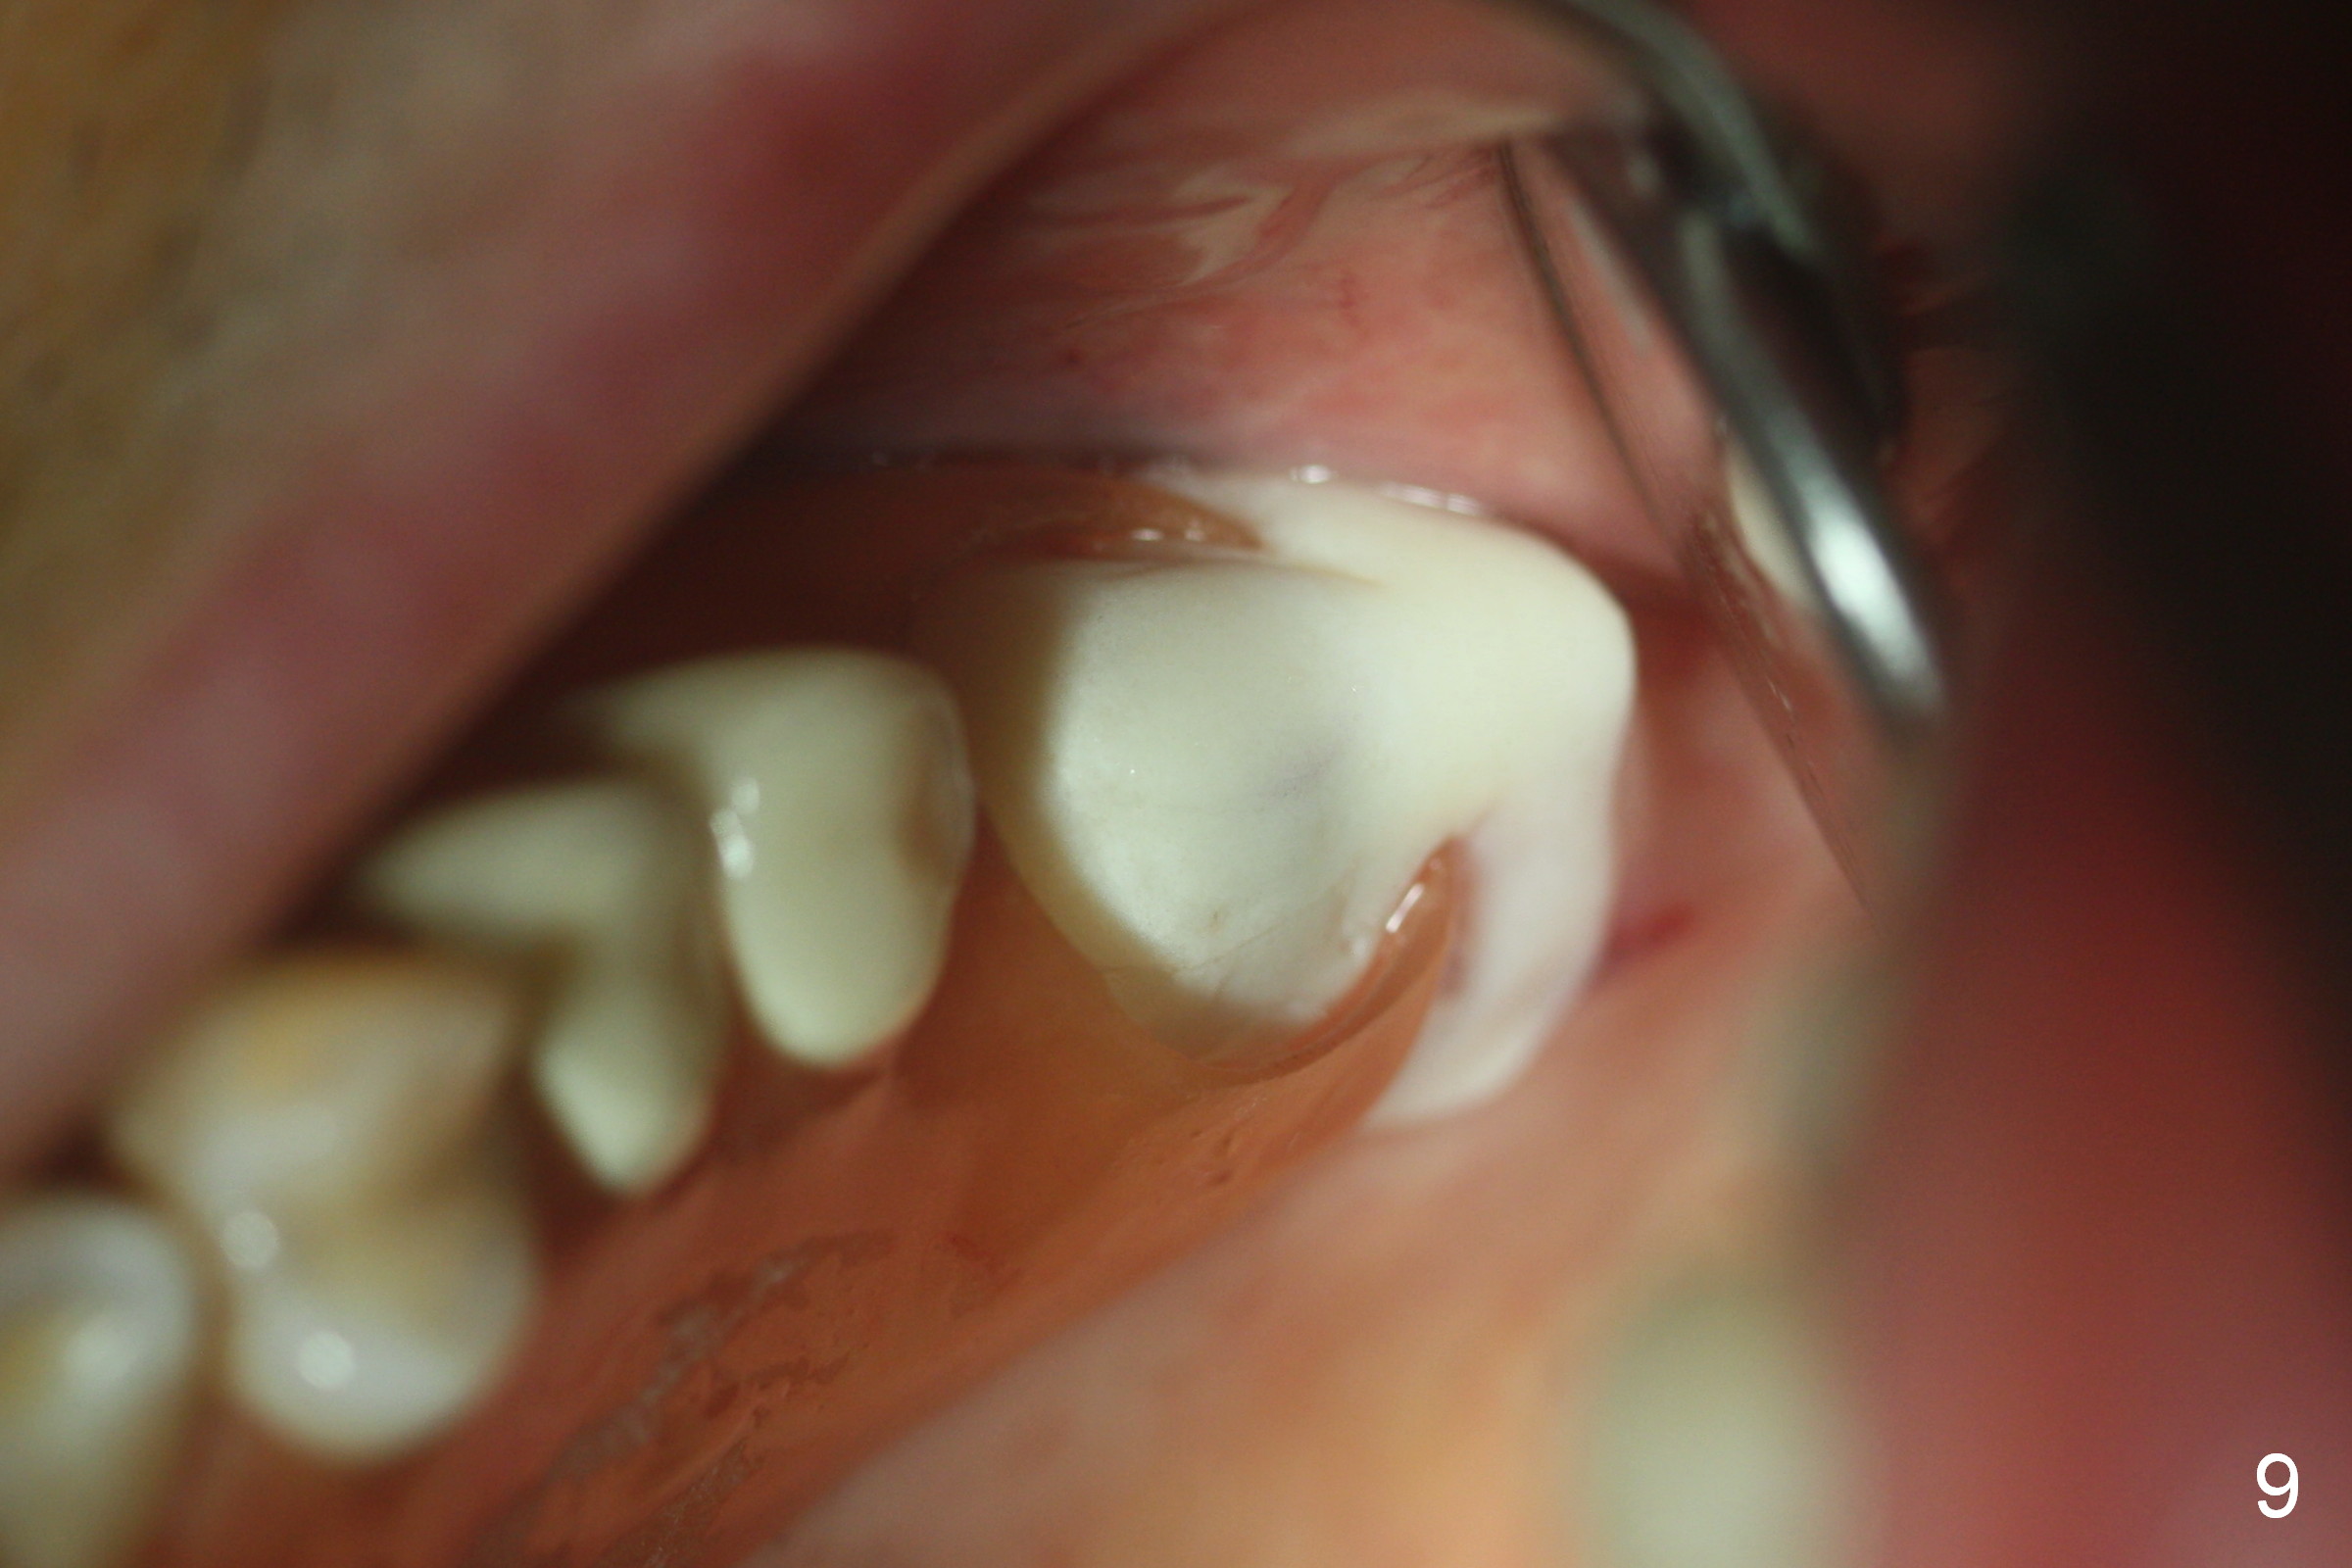

Fig.1,2 show the close relationship of the upper flipper and the residual roots at #15.  Atraumatic extraction using periotomes and surgical sectioning still results in perforation of the mesiobuccal socket (Fig.3 >).  The distobuccal one is shallow, while the septum is small.  It appears that the palatal (Fig.3 P) socket is the most ideal recipient site for the immediate implant and is expanded with Magic Osteotomes until 4.3 mm (Fig.4,5) with the coronal end pushed as buccal as possible.  After placing allograft for sinus lift (Fig.6 >), a 5x11 mm IBS implant is placed with insertion torque ~ 50 Ncm.  A 6x4(3) mm pair abutment is placed, followed by bone graft in the remaining sockets (Fig.6 *) and by Osteogen plug (Fig.7 *).  Finally the socket is sealed by applying acrylic over the abutment (Fig.8).  While the acrylic is setting, the flipper is seated and excess acrylic is removed and pushed away from the flipper (Fig.9).  Advise the patient not to wear the flipper.  If it is being worn, there will be minimal contact between the flipper and the immediate provisional.